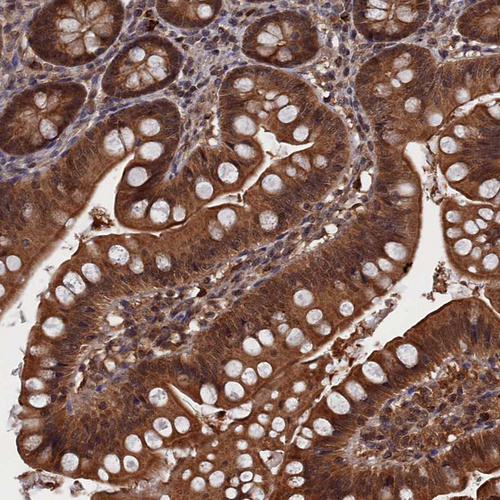

Immunohistochemical staining of human cerebral cortex shows strong cytoplasmic positivity in neurons.